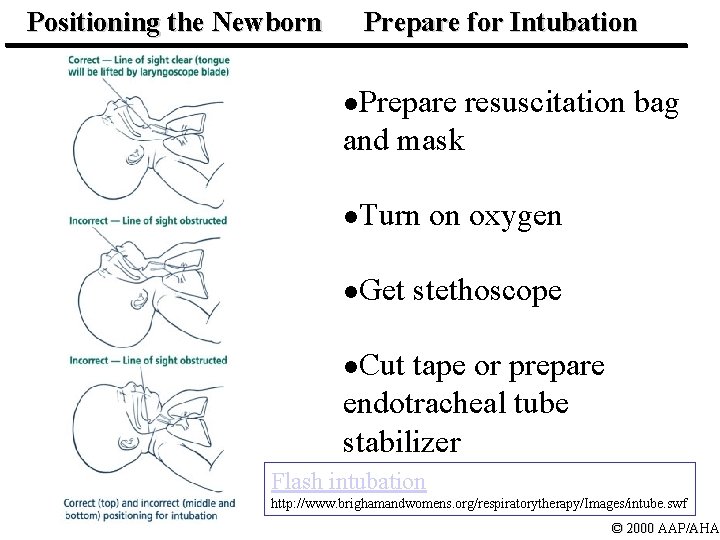

Positioning the Newborn Prepare for Intubation l. Prepare resuscitation bag and mask l. Turn on oxygen l. Get stethoscope l. Cut tape or prepare endotracheal tube stabilizer Flash intubation http: //www. brighamandwomens. org/respiratorytherapy/Images/intube. swf © 2000 AAP/AHA

Lesson 5: Endotracheal Intubation Step 1: Preparation for Insertion l Stabilize head l Provide free-flow oxygen © 2000 AAP/AHA